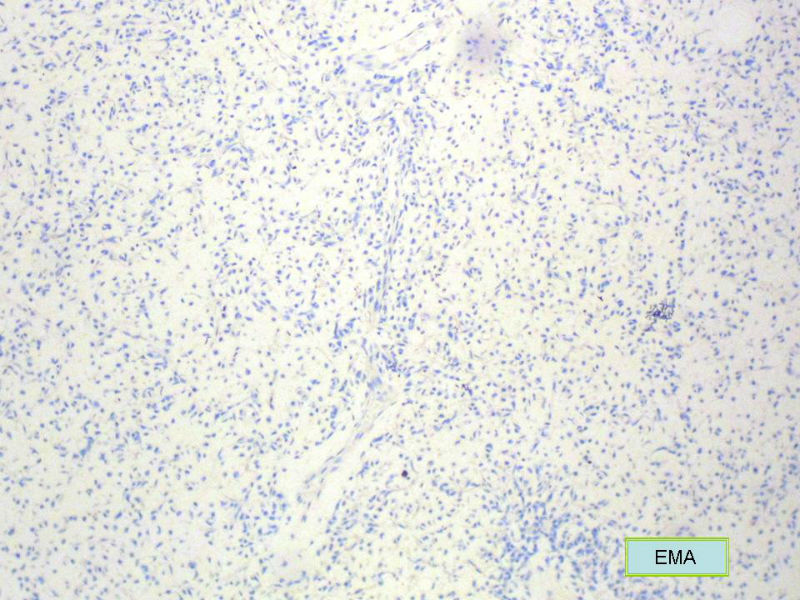

4.组化:1)其它的神经内分泌标记如Syn, NSE? CK?

2)CGA的结果是排除脂肪源性肿瘤或其它肿瘤的有力证据吗?

3. 本例组织学改变与粘液性脂肪肉瘤,粘液样纤维肉瘤,纤维粘液样肉瘤,骨外粘液样软骨肉瘤都有重叠之处,且镜下并未见典型结构。由此,免疫组化结果就尤显重要。特别是专业书籍提到,突触素或嗜铬素阳性,对鉴别诊断有重要意义。我用CGA,也是在以上几个肿瘤中举棋不定而为。NSE和CK没用,其实我想用更多的抗体来证实更多的东西,但患者的经济条件不太好,遗憾!